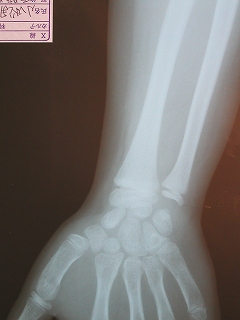

‰E‘O˜rœœÜ

@@”N—î@@8Î@—«

@@•‰“ú@•½¬14”N7ŒŽ27“ú

28Ҝ΋

œÜÇ—á